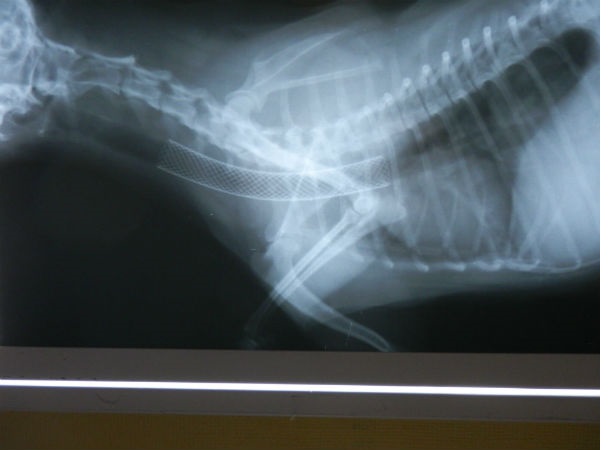

Для диагностики коллапса, ранее, стандартом считалось 2 боковых рентгеновских снимка грудной полости в разные фазы дыхания. Во время вдоха проявляется коллапс шейного отдела трахеи, во время выдоха- грудного. Из-за того, что у собак стресс при посещении ветеринара, сложно порой поймать нужную фазу дыхания и сделать снимок. Приходится делать их больше, тем самым увеличивая дозу облучения. При чрезмерном загибе вверх шеи на снимке мы увидим уплощение трахеи.

В нашей клинике, благодаря инновационным методам и материалам, а также эндоскопической технике можно без операции, через естественное отверстие вставить эндо трахеальный стент.

Стент это такое устройство, которое не позволяет трахее смыкаться. Это каркас из специального пластика, который имеет свойства врастания в слизистую трахеи.

Стент поставляется в стерильной упаковке в сложенном виде в устройстве доставки. Внутри доставляющего устройства есть отверстие для подачи кислорода. Чтобы во время установки животное могло дышать. Под визуальным контролем эндоскопа стент ставится в нужное место и медленно распрямляется, расширяя трахею. Устройство доставки извлекается, а стент остается стоять и удерживать трахею от смыкания.